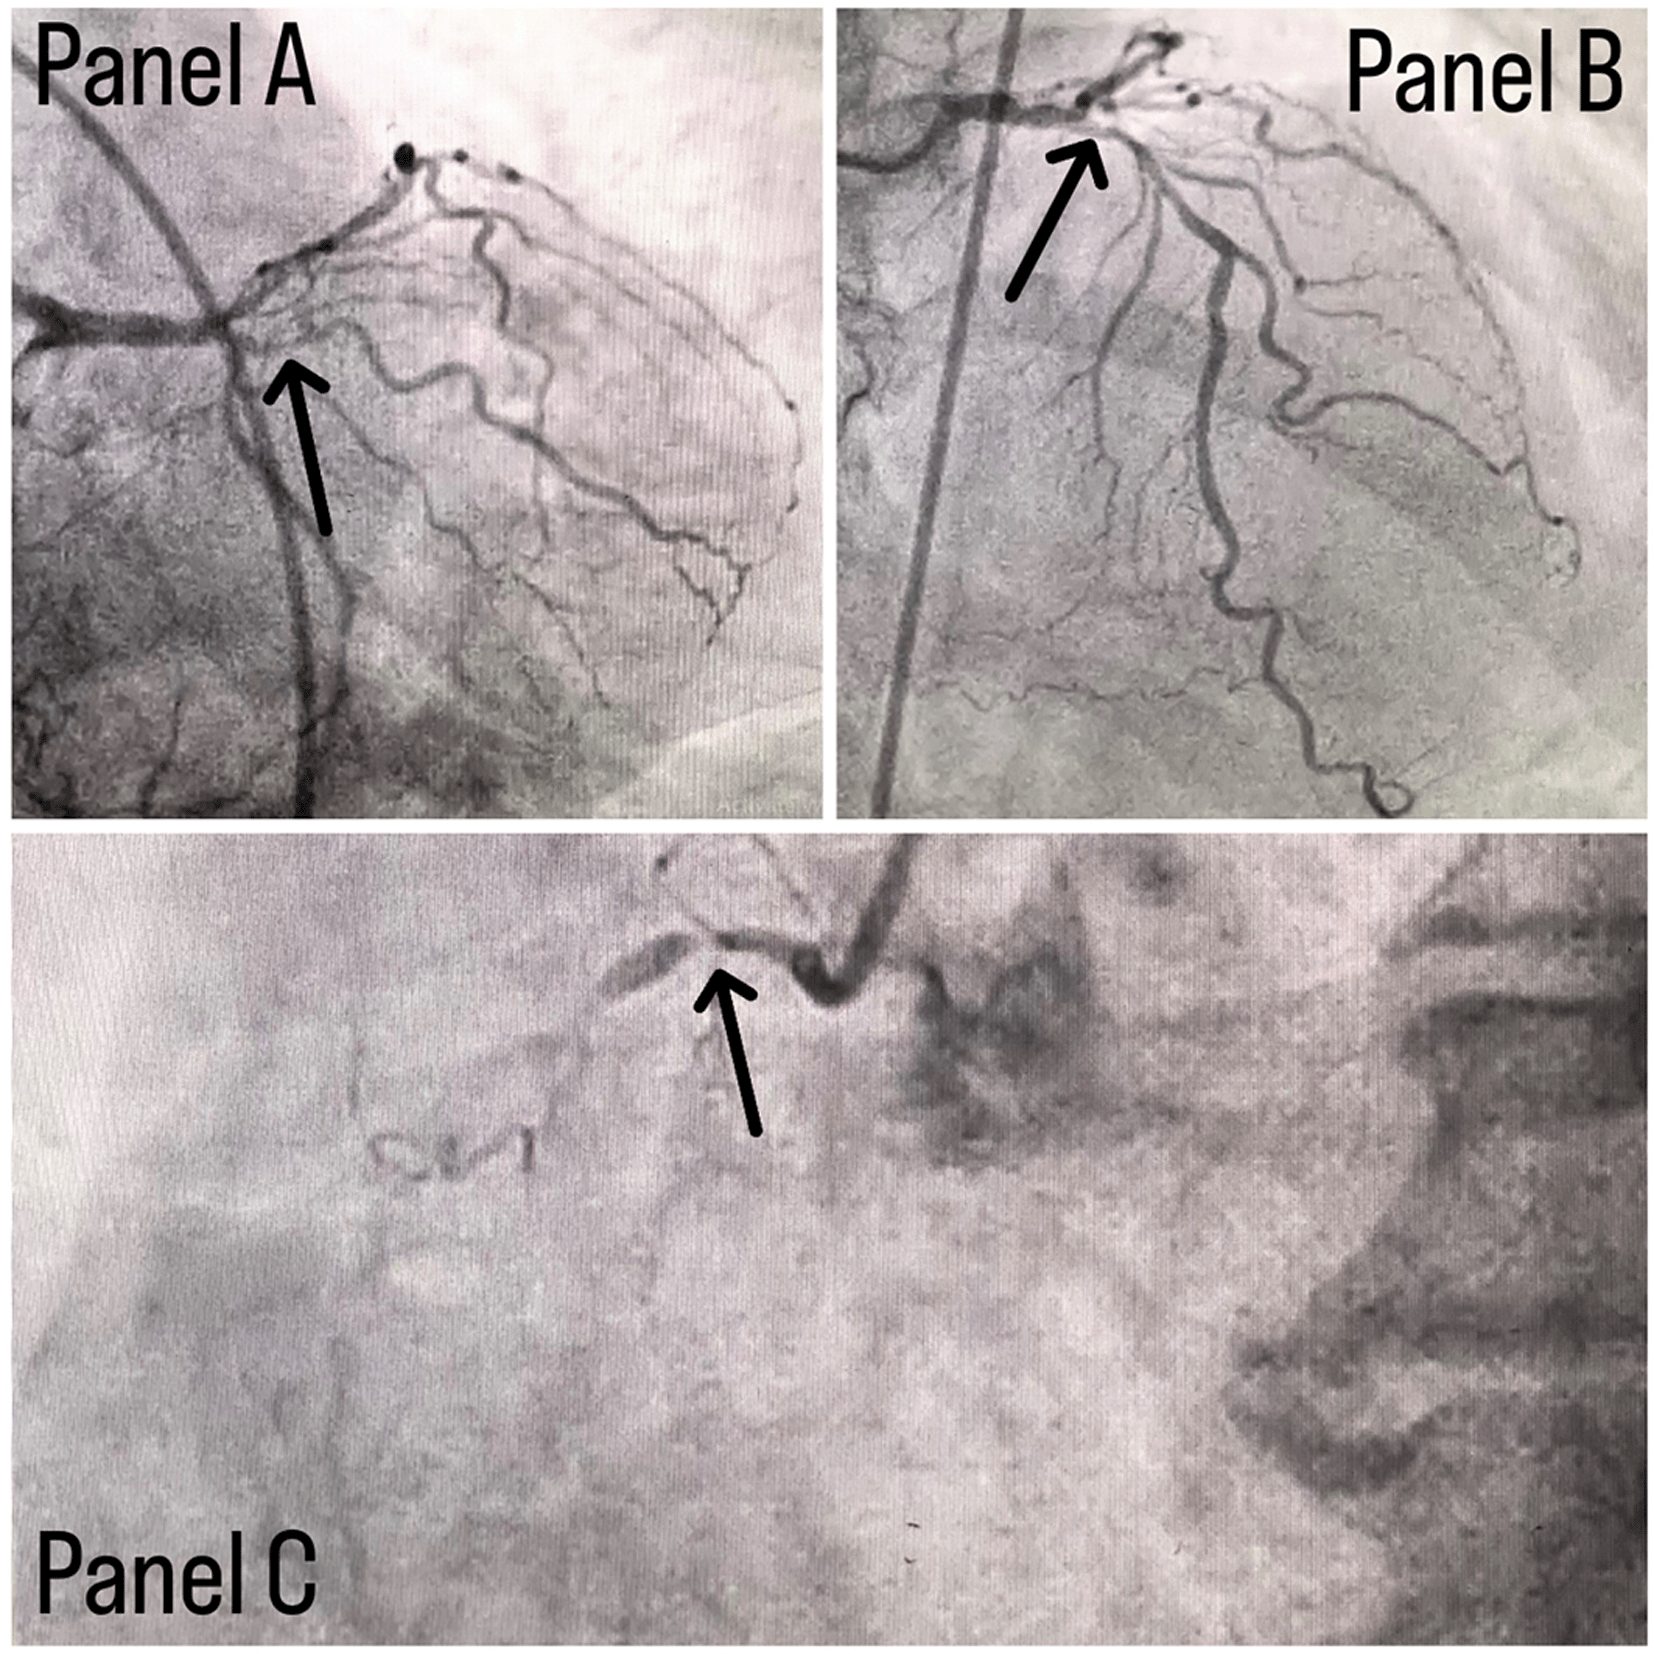

Coronary angiography was done and a triple vessel coronary artery disease was diagnosed as shown in Figure 1. A subclavian puncture was taken to look for a subclavian artery considering the claudication symptoms of the patient and peripheral vascular disease was diagnosed with bilateral subclavian artery stenosis as shown in Figure 2. Considering the severity of claudication pain in our case, bilateral renal and femoral arteries were also checked via aortic flush and bilateral renal artery ostial stenosis was seen, as shown in Figure 3, while the femoral arteries appeared normal bilaterally.